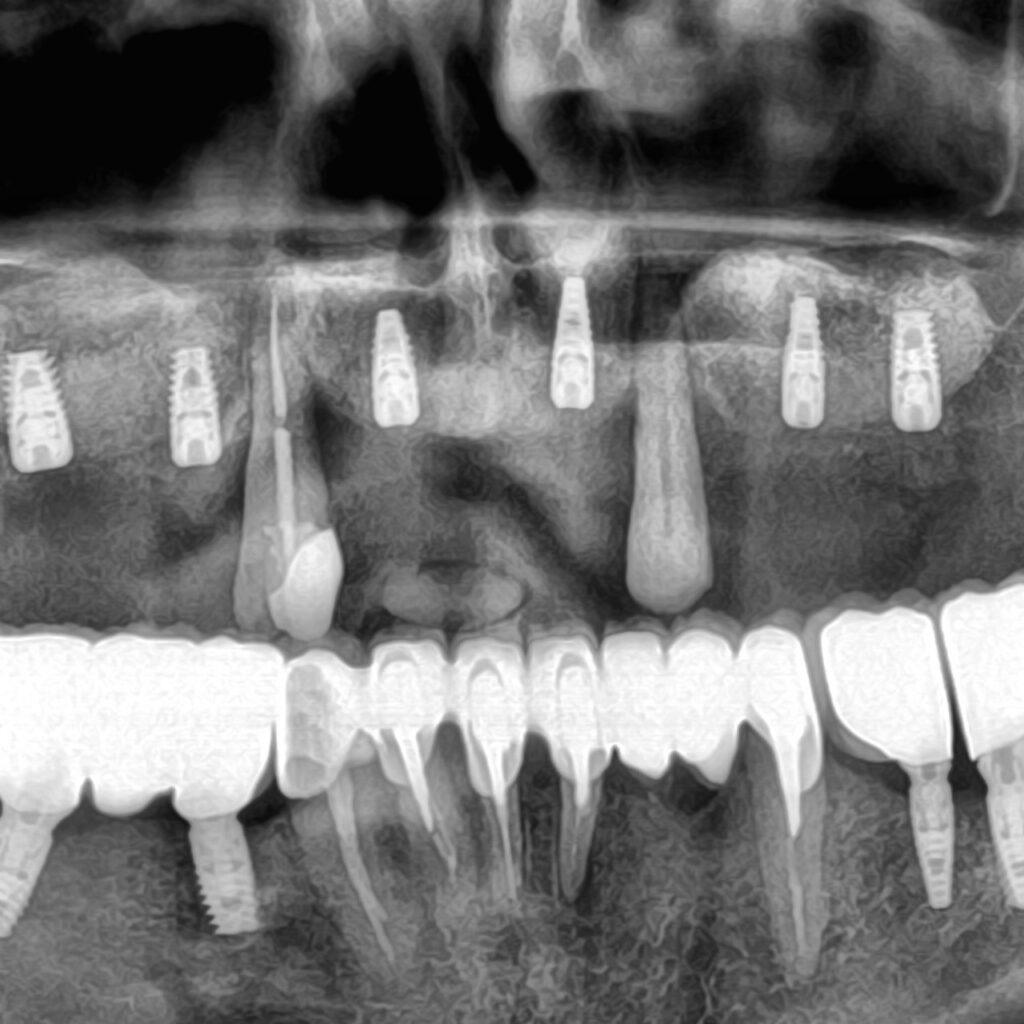

Robimy zdjęcie 3D, oceniamy stan kości i przedstawiamy opcje z cenami. Bez oceniania. Bez pospieszania.

Efekt na lataStałe zęby na 6 implantach zamiast ruchomej protezy. Wszystko zaplanowane z góry, bez niespodzianek.

Brakuje wszystkich zębów → SAFE ARCH (stałe zęby na 6 implantach)